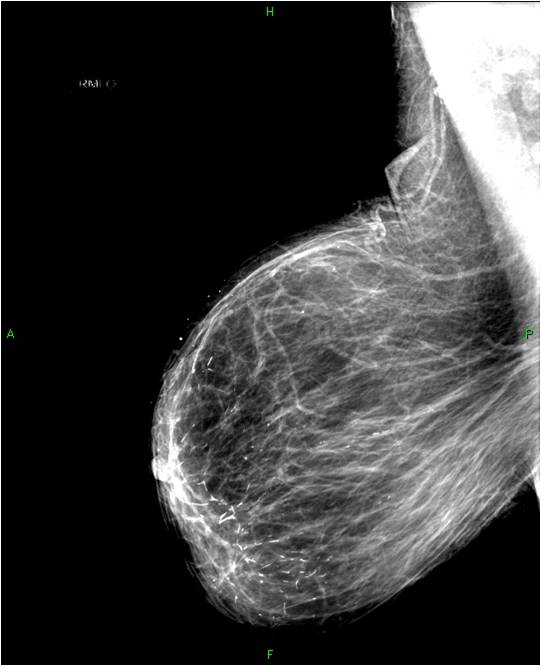

2. Digital mammography has displaced the analogue technic for today almost everywhere: (pictures 1,2,3) phosphorous plate or direct digital methods. For breast imaging the latter is the method of choice. Phases of image production separate. The image is produced on the detectors, but appears on the high resolution monitor and can be stored as a digital data set at various storage mediums (e.g.: CD, hard disk drives).

Image

Picture 1.